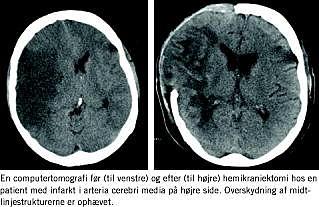

De fleste kender vel forløbet af et malignt mediainfarkt. En patient indlægges efter en pludseligt opstået facialisparese, hemiparese, hemianopsi og kognitive udfald, men er i øvrigt vågen. En computertomografi (CT) afslører ingen cerebrale forandringer ud over måske hyperdensitet i arteria cerebri media, hvilket er forenelig med tromboemboli. I løbet de næste døgn forværres patientens tilstand med faldende bevidsthedsniveau, og en skanning afslører nu et komplet mediainfarkt med ødem og overskydning af midtlinjestrukturerne. Tilstanden forværres yderligere, hvorefter patienten dør med cerebral inkarceration. Behandlingsmulighederne er i denne situation få, idet den kendte intensive behandling af forhøjet intrakranialt tryk har vist sig at være uden effekt.

Princippet i behandlingen er at give infarktet plads til at ekspandere ud under huden for derved at reducere det intrakraniale tryk og sikre tilstrækkelig perfusion i både den raske del af hjernen og infarktets randzoner.

Såfremt patienten under den efterfølgende observation på en neurointensiv afdeling viser sikre tegn på faldende bevidsthedsniveau, foretages der hemikraniektomi med fjernelse af en stor kranieknogle over det infarcerede område, ligesom dura åbnes. Knoglepladen gemmes for at blive replaceret, når det cerebrale ødem er aftaget.

Vi håber med denne statusartikel at kunne udbrede kendskabet til denne behandlingsform (Figur 1 ).